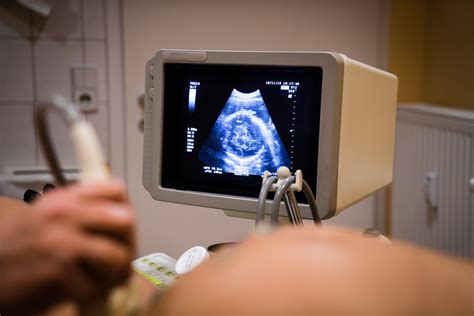

- Transvaginalinis ultragarsas: Tai pagrindinis diagnostikos metodas. Jis leidžia pamatyti gimdos ertmę, įvertinti gestacijos maišelio dydį, ar yra embrionas ir ar jo širdis plaka. Įprastai širdies plakimas tampa matomas apie 5,5-6 nėštumo savaitę.